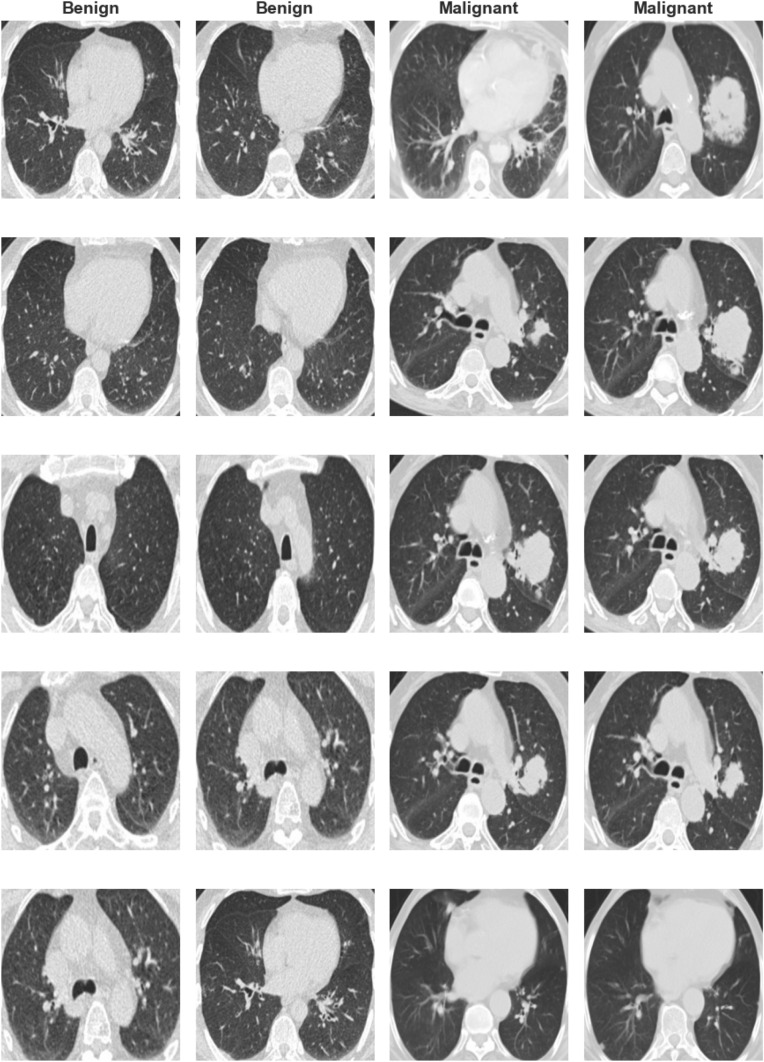

Figure 1 illustrates the study workflow, while Fig. 2 displays representative CT scan images, highlighting malignant (cancerous) and non-cancerous cases. The malignant images reveal abnormal lung parenchyma growths with irregular shapes and densities, whereas non-cancerous images show normal pulmonary structures without abnormalities.

Fig. 2.

Examples of malignant and non-cancerous cases in CT scans